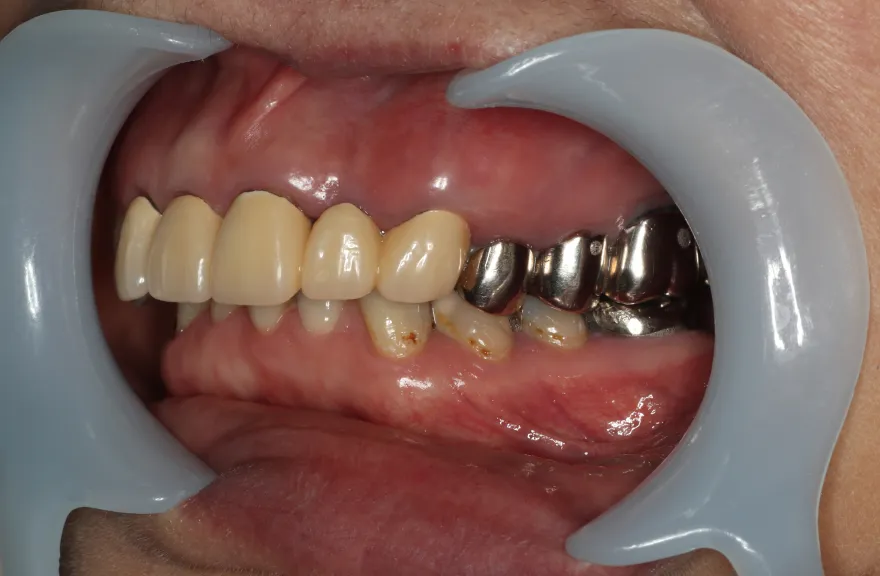

右上の奥歯が取れたということで来院されました。

各所の金属は昔に治療されたもので、外してみるとどれも虫歯になっていました。

一つずつ虫歯治療を行い、インプラント治療、矯正治療を並行して行いました。 - 治療費用・方針

写真の通りに治療を終了いたしました。

各所虫歯に侵食されていましたが、歯を残すことができたのでインプラントの数をおさえることができました。

下の前歯が先天的に1本欠損しており、そのため噛み合わせを構築することが難しいケースでした。矯正治療を併用することで前歯と奥歯をバランスよく噛ませることに成功しました。